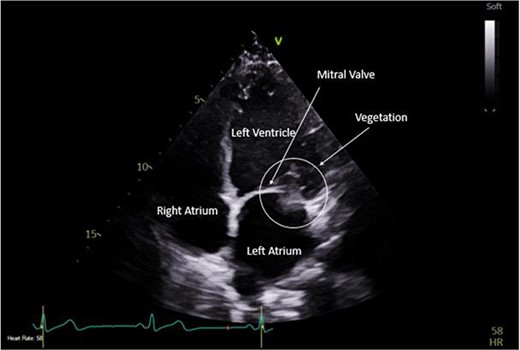

Intra-operatively, femoral–femoral bypass was established and a 3 cm windsock vegetation was found with a 1.5 × 1.5 cm hole at the aortic inlet on the annular junction. The vegetation travelled from the LV to LA as shown in Figs 3 and 4. The vegetation was excised and the valve debrided, which resulted in moderate regurgitation from severe. Hence, a further 26 mm Physio II ring was placed resulting in no mitral regurgitation. The excised vegetation is shown in Fig. 5 and the post-op TTE images are shown in Figs 6 and 7.